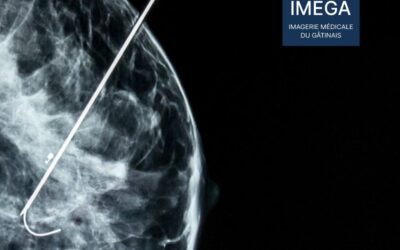

Interventionnel Mammaire : Pose de Repère sous Échographie

Découvrez la pose de repère sous échographie, une technique d’interventionnel mammaire précise et moins invasive. Apprenez-en plus sur ses avantages, sa procédure et son rôle dans le diagnostic des anomalies mammaires.